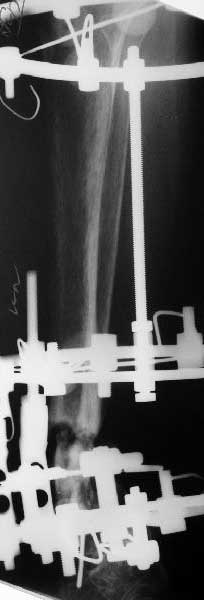

Глубокоуважаемые коллеги,Поступила женщина 72 лет. Полтора года назад - укушенная рана, перелом голени. Лечили аппаратом, не срослось. Долго не заживала рана.

Но вроде уже с полгода мягкие ткани закрыты. Спереди подпаянные рубцы. Есть приличная подвижность на уровне несращения. Картинки в приложении. Что предложите? Спсибо заранее.

Вроде бы ты когда-то писал, что аппарат решает проблемы, или аппаратом лечили где-то в другом месте?

Какова подвижность в голеностопе? Если движений в суставе практически нет (о чем можно предположить по Ргграмме) и инфекция исключена, я бы подумал о ретроградном штифтовании через таран.

В общем, начали c аппарата - нложили, малоберцовую внизу пересекли, выбрали люфт, раз дальше сопротивление пошло - выведем постепенно.

Картинки приложены. Жду комментариев.